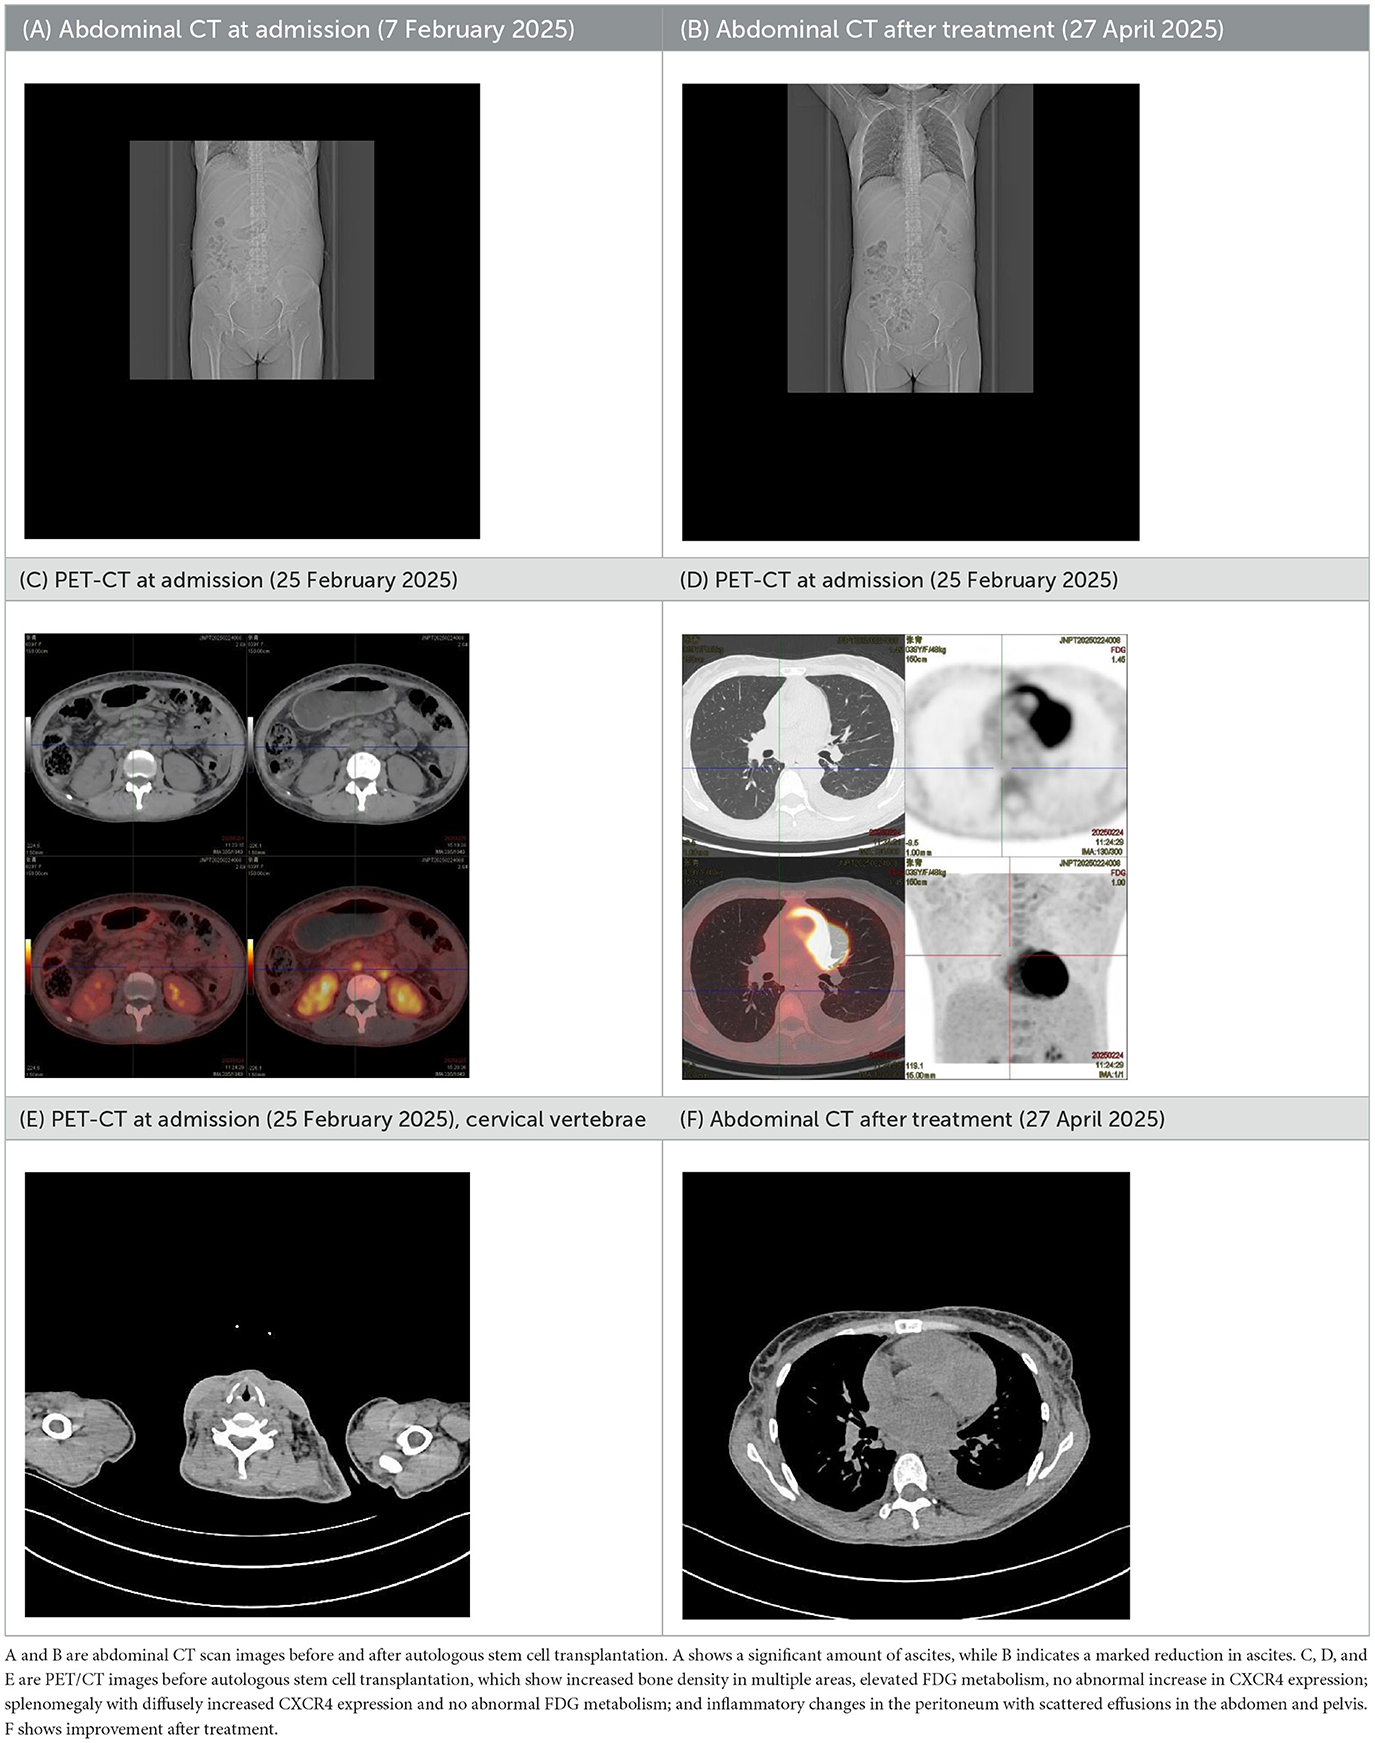

| (A) Abdominal CT at admission (7 February 2025) | (B) Abdominal CT after treatment (27 April 2025) |

|---|---|

| (C) PET-CT at admission (25 February 2025) | (D) PET-CT at admission (25 February 2025) |

|

| (E) PET-CT at admission (25 February 2025), cervical vertebrae | (F) Abdominal CT after treatment (27 April 2025) |

CT images of the patient's abdomen.

A and B are abdominal CT scan images before and after autologous stem cell transplantation. A shows a significant amount of ascites, while B indicates a marked reduction in ascites. C, D, and E are PET/CT images before autologous stem cell transplantation, which show increased bone density in multiple areas, elevated FDG metabolism, no abnormal increase in CXCR4 expression; splenomegaly with diffusely increased CXCR4 expression and no abnormal FDG metabolism; and inflammatory changes in the peritoneum with scattered effusions in the abdomen and pelvis. F shows improvement after treatment.